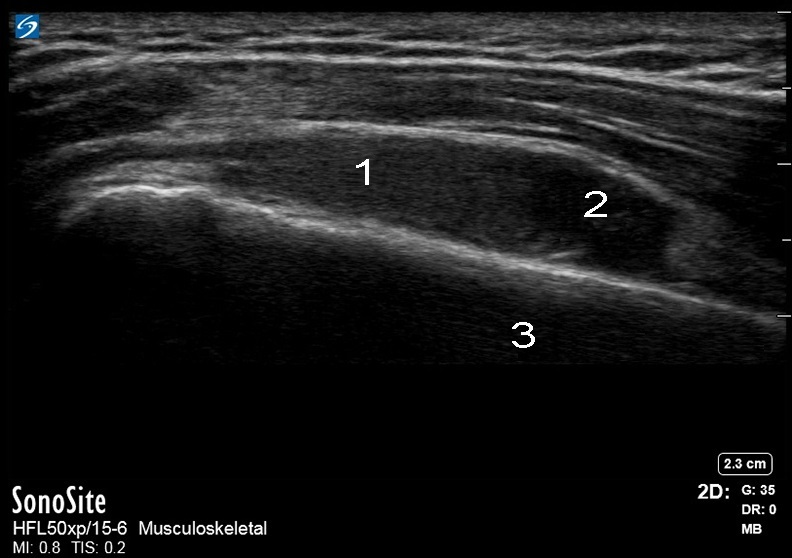

Imagen de señal en forma de gota subacromial lateral del hombro

1. Bolsa

2. Líquido simple

3. Cuello SX del húmero lateral